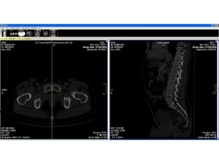

Una nueva técnica permite deducir el sexo y edad de un cadáver a partir de imágenes del pubis 09/01/2013

Científicos de la Universidad de Granada han desarrollado una nueva técnica informática que permite determinar la edad y el sexo de un cadáver con una fiabilidad del 95 por ciento, a partir de un software de descarga gratuita denominado ImageJ y un visor DICOM, también gratuito, denominado K-Pacs. Este nuevo sistema, pionero en el mundo, se aleja de las técnicas clásicas de observación macroscópica de las características osteoarticulares que se emplean tradicionalmente al realizar una autopsia, y resulta mucho más rápido y sencillo. Para desarrollar su investigación, los científicos analizaron 169 archivos procedentes de TAC hospitalarios facilitados por los Servicios de Salud Centrales de Castilla la Mancha (SESCAM), de hombres y mujeres de entre 17 y 90 años. En concreto, el sistema analiza imágenes del pubis. El autor principal de este trabajo es Manuel López Alcaraz, investigador del Laboratorio de Antropología Forense de la Universidad de Granada. “La edad y el sexo son dos parámetros fundamentales en la Antropología Forense para identificar un cadáver, y el pubis, una región ósea de reconocido interés al respecto. En nuestro estudio, hemos aprovechado la mayor capacidad que tienen los ordenadores para discriminar entre niveles de grises en un histograma (el ojo humano sólo discrimina 64), poniéndolo en relación con la edad y el sexo”. El investigador destaca que esta técnica podría aplicarse a la virtopsia o autopsia virtual. “En la actualidad, el principal inconveniente de este tipo de autopsia es que, de momento, no puede sustituir al análisis microscópico de los tejidos para conocer las patologías padecidas, si una lesión es vital o postmortal, los días de evolución de una lesión... El presente método, al estar basado en el análisis de imagen, puede intentar aplicarse a la virtopsia para tratar de dar respuesta a muchas más preguntas de las que actualmente puede resolver”. Este trabajo, además, ha roto con la tendencia clásica de la Antropología Forense de que el pubis resulta de utilidad sólo en el rango de 20 a 40 años, “porque hemos conseguido muy buenos resultados para identificar a personas mayores de 50 años, especialmente en el sexo masculino”, destaca el autor. Más información Universidad de Granada